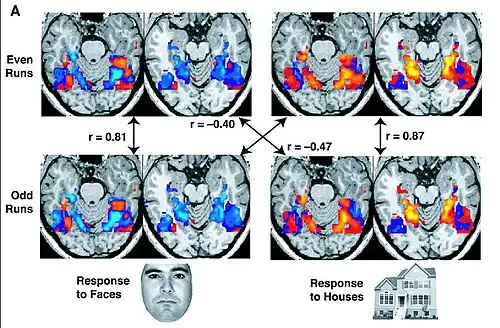

L’IRMf est parfois considérée par ses détracteurs comme une forme moderne de la phrénologie, cette théorie qui considère que les bosses du crâne sont le reflet du caractère d’une personne[5]. Les belles images obtenues par l’IRMf lui valent aussi le surnom de « blobology », « la science des taches de couleur », en ce sens que la technique permet bel et bien de savoir, par exemple, qu’une tâche langagière est corrélée avec une activation dans l’hémisphère gauche, mais sans confirmer que cette activation est due, par exemple, directement au traitement du langage ou plutôt au simple fait de porter attention à un écran. Selon Peter Bandettini, on ne peut pas inférer une causalité simplement parce qu’on connait l’endroit d’activation[9]. Plutôt que de simplement observer des tâches, certains chercheurs utilisent plutôt l’analyse multivariée qui permet d’analyser le comportement d’unités plus petites que les tâches : les voxels. De cette façon, des informations qui ne semblaient être que du bruit se transforment en signal[9].

Interprétation des données (principe de construction des images cérébrales)